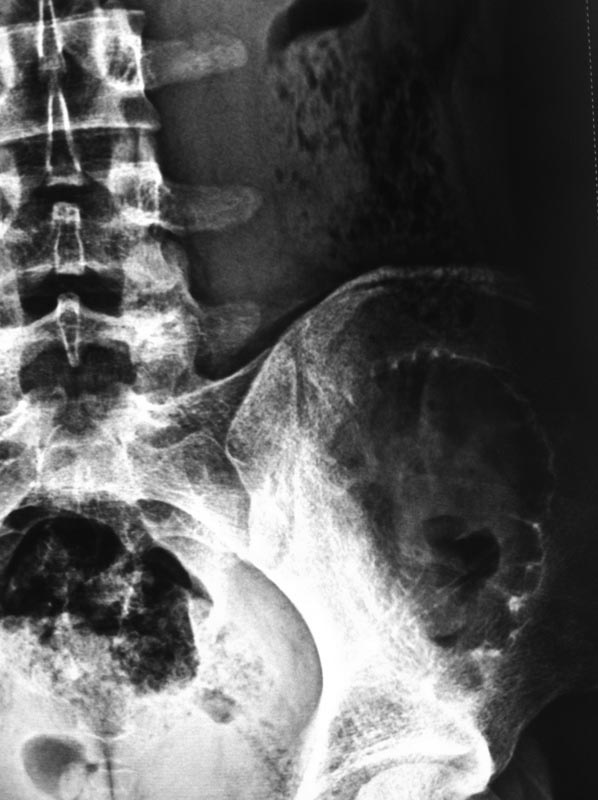

[Ortho] Киста подвздошной кости

Пациент 15 лет, спортсмен, внезапно появились боли в подвздошной области

слева при поворотах и наклонах туловища. В покое ничего не беспокоит.

Пациенту в ЦИТО была выполнена трепан-биопсия образования,

гистологически ничего плохого не выявлено. Хотят оперироваться в

Махачкале. Возникает два вопроса: 1)каким доступом пойти? 2)чем

заполнять? Доступ проще всего сделать наружне-боковой по гребню

подвздошной и дальше трансосально до полости. Полость очень большая,

аутокости слишком много брать, I-Factor и Силориф если брать 60-90 куб

см выходит на 100-200 тысяч, пациент не рентабельный так сказать. Если у

кого был такой случай в практике, просим совета. И еще вопрос: зона не

опорная, нельзя ли заполнить полость костным цементом ? Как при

гемангиоме тела позвонка.